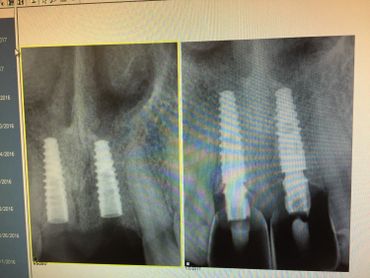

The Neodent GM Guided Surgery Kit is a compact, easy to use guided surgery system. Clinicians can provide CT scan, digital photos, and impressions to a laboratory for precise implant guide fabrication. Temporary teeth can be made and the lab will know the depth, angle, and timing of the connection of the implant. This allows you better esthetics and provides the patient teeth the same day with less chair time.

The Dental Future Center, Dr Bernee Dunson, and 3DDX Implant Guided Surgery course.